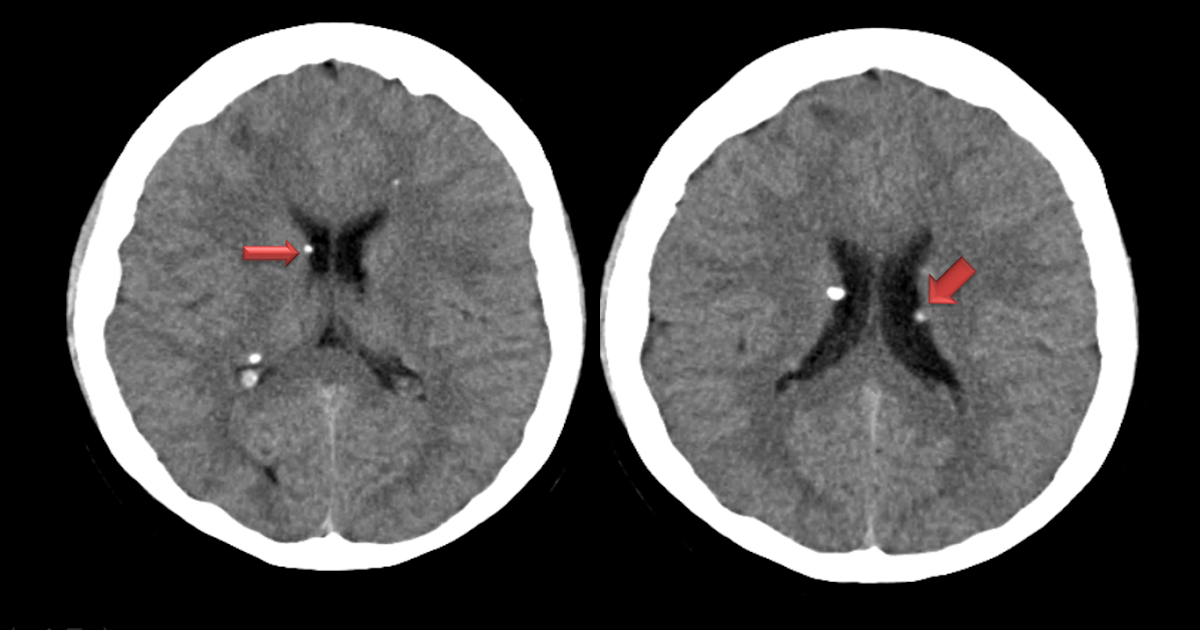

Computed tomography of the brain showing periventricular tubers (arrows

Computed tomography of the brain showing periventricular tubers (arrows Tubers On The Brain Cortical tubers or subcortical tubers (with involvement of the underlying white matter) are a common finding in tuberous sclerosis,. There are three main anatomical features associated with tsc that alter the structure of the brain: These hard ‘lumps’ are the reason for the. The cortical tuber (from which tsc was originally named) is a disorganized area of the. Tuberous sclerosis. Tubers On The Brain.

Computerized tomography (CT) of the brain showing bilateral Tubers On The Brain Cortical tubers or subcortical tubers (with involvement of the underlying white matter) are a common finding in tuberous sclerosis,. Tuberous sclerosis (ts) growths, called tubers, are often found growing inside of the brain and retinal area of the eye. Tuberous sclerosis complex (tsc) is a congenital disorder caused by a defective. There are three main anatomical features associated with tsc. Tubers On The Brain.